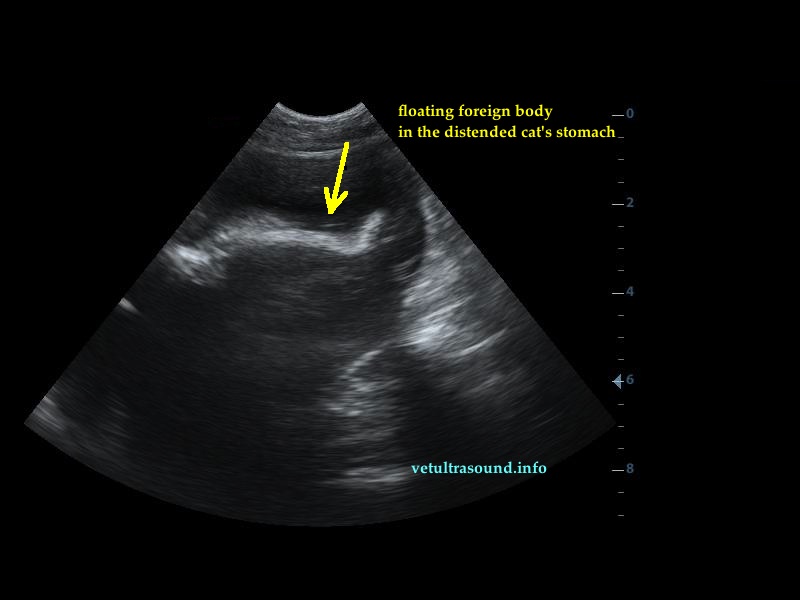

Findings: There was dilation of the stomach and the proximal duodenum. The dilation was caused by a foreign body(pic2). Inside the stomach there were also other foreign bodies floating around(pic1).

pic 1